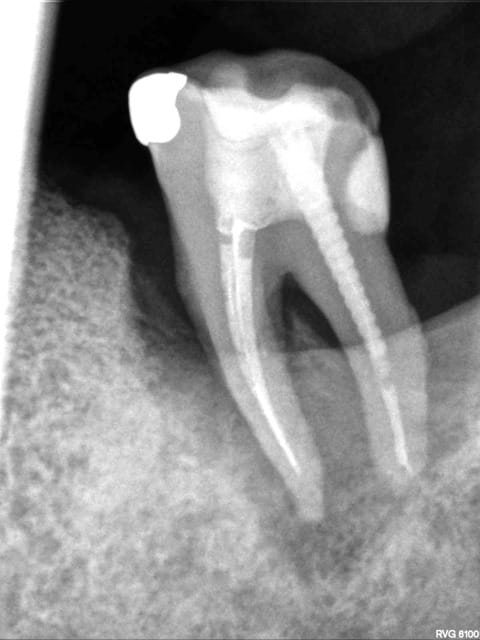

Petite présentation rx pour savoir ce que vous pensez de ce cas. R26 = 14/10/2010

R26 szlxny - Eugenol